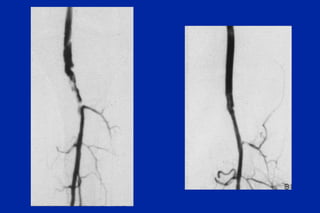

Este documento resume los principales tipos y técnicas de angiografía. Describe brevemente la angiografía, arteriografía, flebografía y linfografía, así como las técnicas de contraste y materiales utilizados. También explica los principales accesos vasculares, la técnica de Seldinger, la angiografía por sustracción digital y algunas técnicas endovasculares comunes.